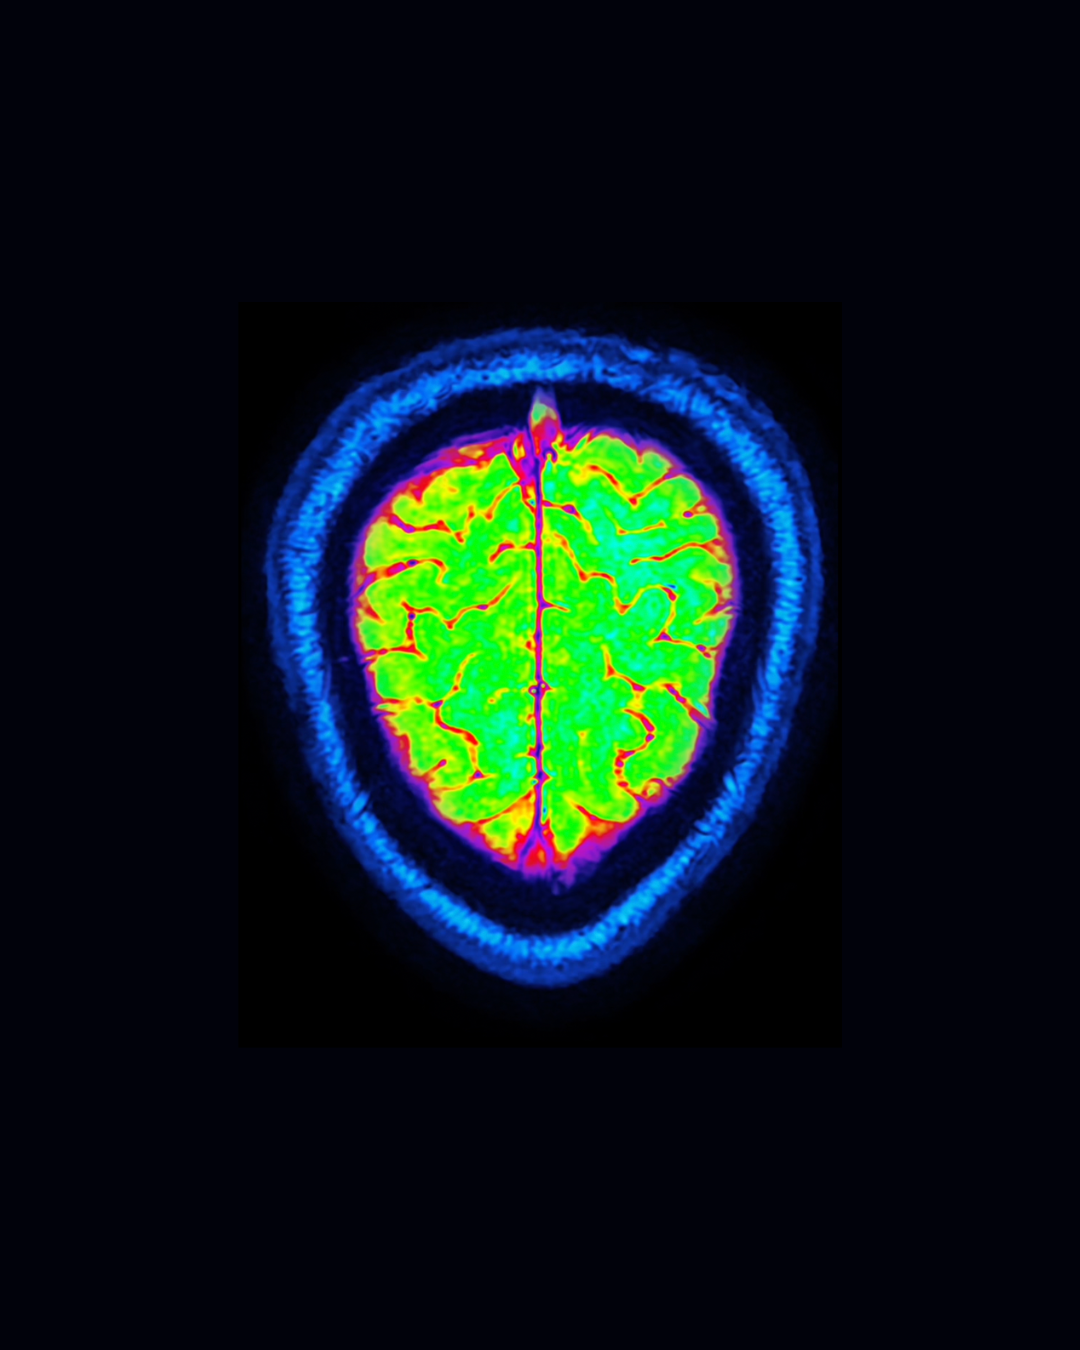

Neuroimaging Showed Differences in PMDD

In a 2022 study, researchers in Sweden used advanced MRI scanning on 89 women with PMDD and 42 healthy controls during the luteal phase (5). They discovered striking structural differences between those with PMDD and those who did not have PMDD.

• Women with PMDD had smaller gray matter volume in ventral posterior cortices and the cerebellum compared to controls.

•Women with PMDD had smaller volumes in the right amygdala and putamen compared to controls.

• A thinner cortex was observed in women with PMDD compared to controls across widespread brain regions, particularly in the left hemisphere. This wasn’t a small difference - effect sizes ranged from moderate to large.